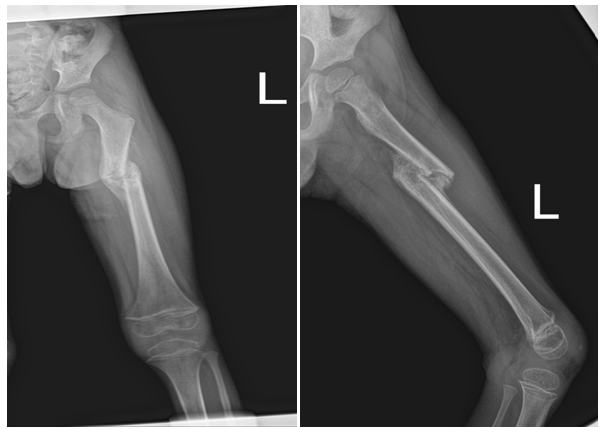

As part of primary survey patient’s chest and pelvis X-rays done at trauma bay shows no abnormality. AP and lateral X-rays of left femur showing hip and knee joints were reviewed by different ranked orthopaedics surgeons with agreement of normal x-ray impression (Figure 1 & 2). The following visits for the same complain has different x-rays with same impression of normal x-ray (Figure 3). Except for the one at last visit with the clinical evidence of deformity, patient has diaphysial femur fracture (Figure 4 ).

Figure 1 Anterior, posterior pelvis x-ray showing left hip.

Figure 2 Posterior, anterior and lateral chest x-ray of left femur showing knee.